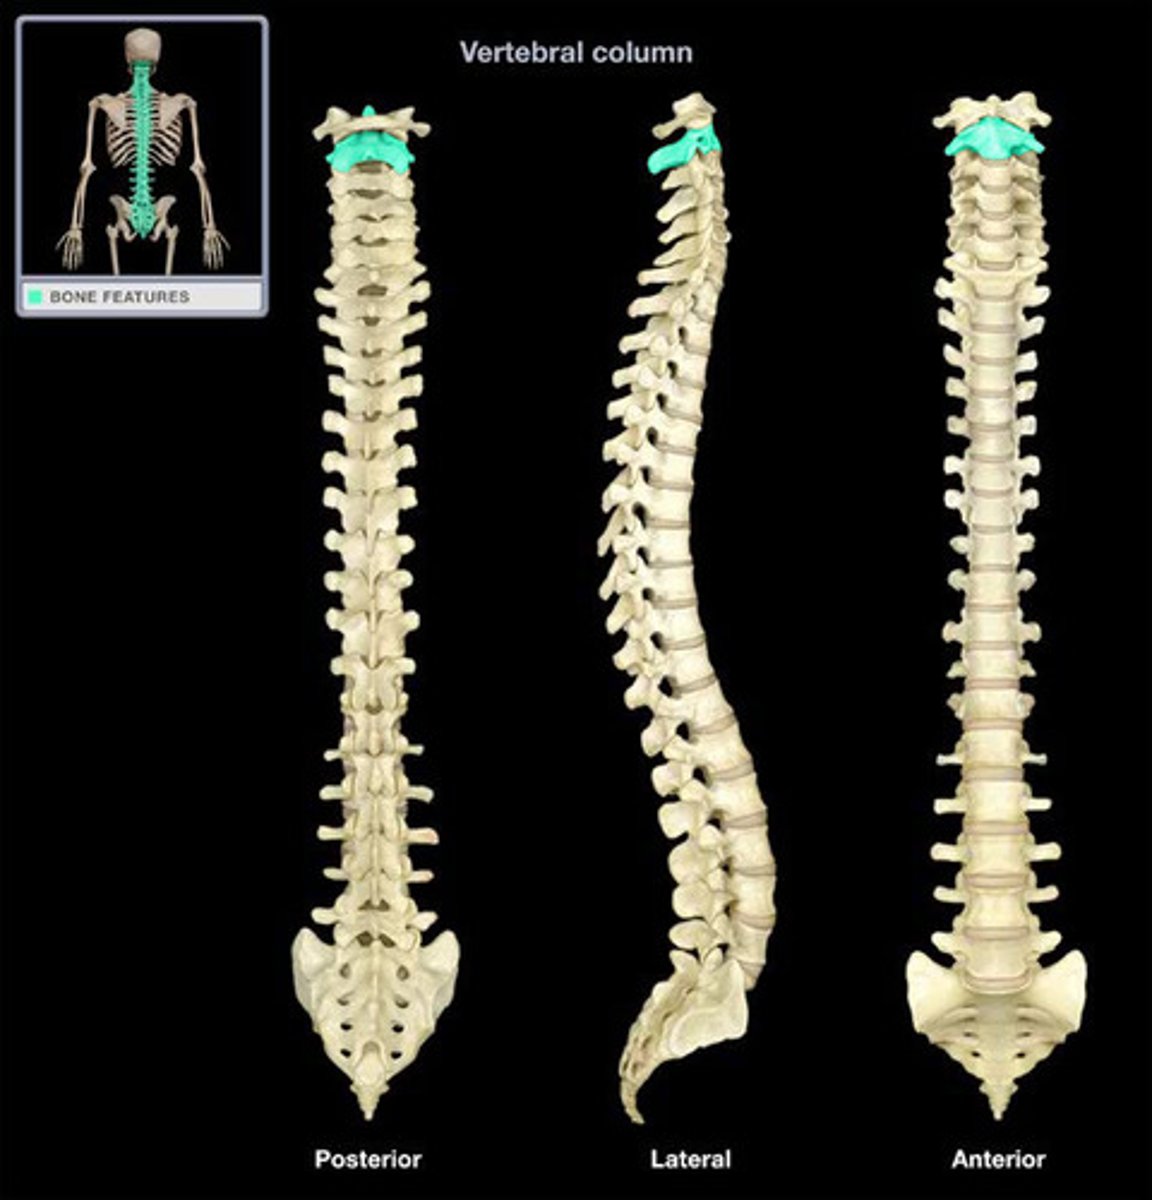

cervial lordosis (convex forwards)

thoracic kyphosis (convex backwards)

lumbar lordosis (convex forwards)

sacral kyphosis (convex backwards)

L4

at what level is the ilac crest

T2

at what level is the sternal notch

what are the vertebral ranges for the pelvic region

s1 up til diaphram

what are the vertebral ranges for the abdominal region

diaphram to shoulder

what the ranges for the thoracic region